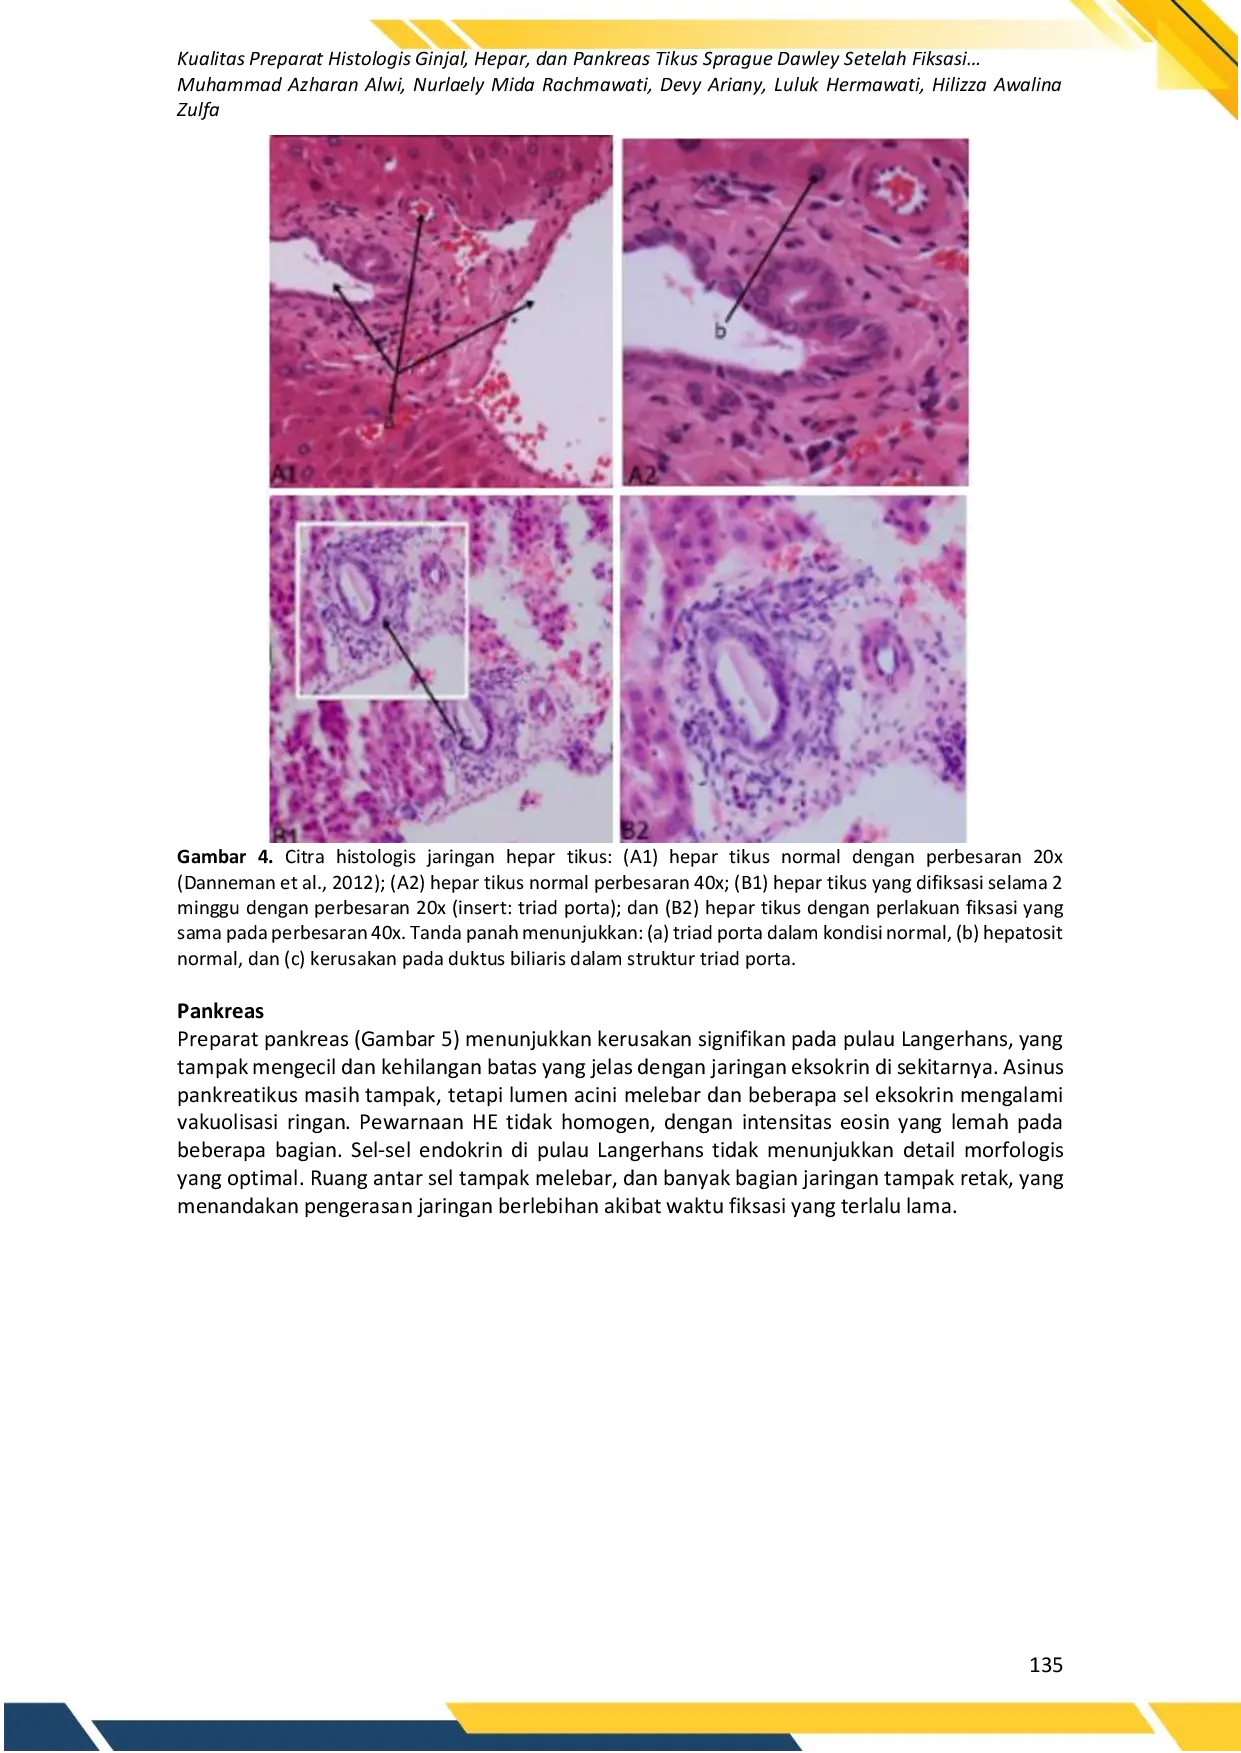

UWKSUWKS Fiksasi selama dua minggu tidak menghasilkan preparat histologis yang optimal, sehingga waktu fiksasi ini tidak disarankan sebagai acuan dalam penyusunanFiksasi selama dua minggu tidak menghasilkan preparat histologis yang optimal, sehingga waktu fiksasi ini tidak disarankan sebagai acuan dalam penyusunan